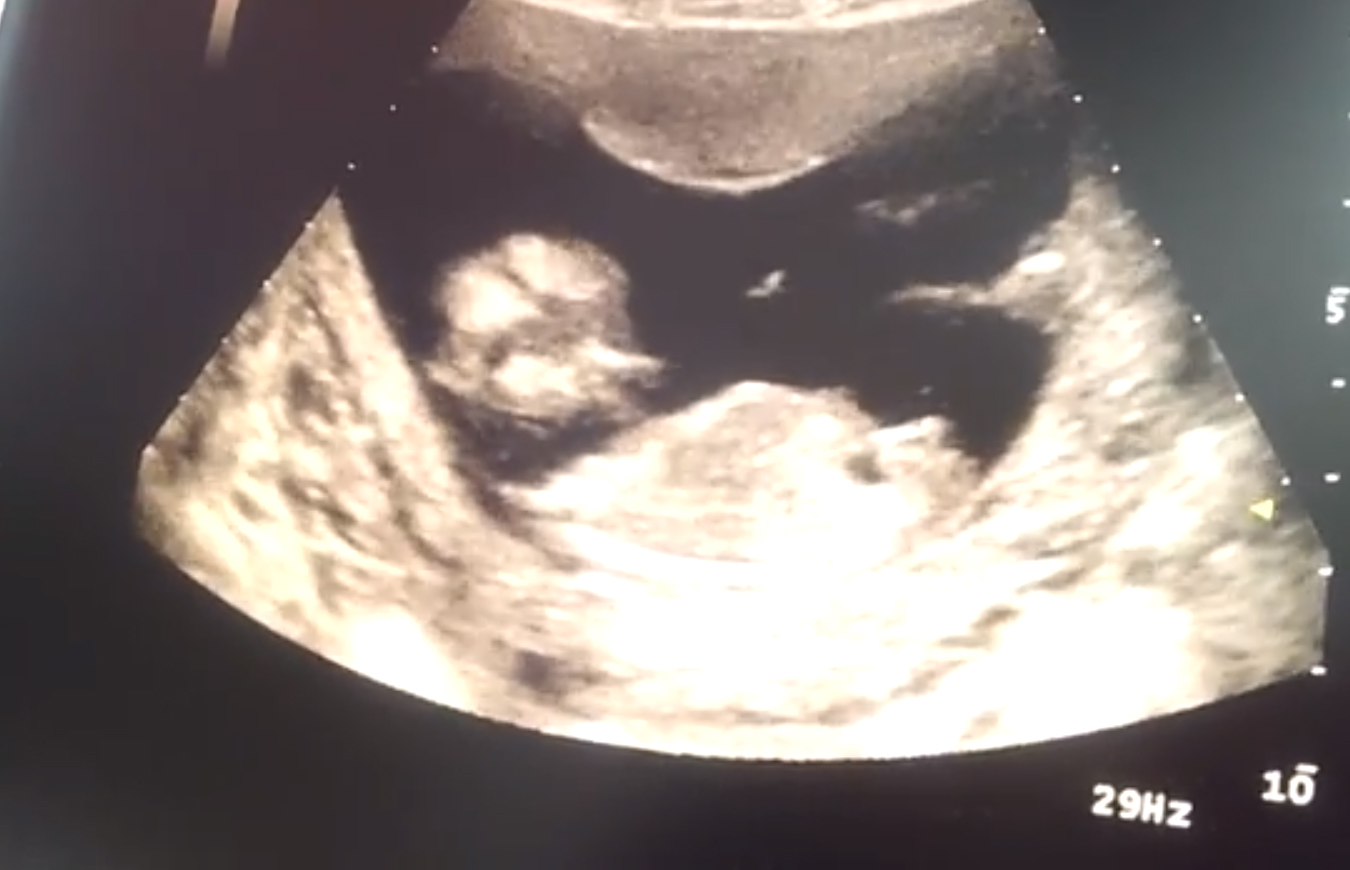

Hello! :D I am Stefania and i was hoping if someone can see/guess if i'll get a boy or a girl.

On the photos i am 14.5weeks. Thanks already!

Boy

I would guess boy

That's so tough I actually thought girl at first but going 50/50 x

For gestation, I would guess girl. I would think a boy would be 90 degrees up at this point. But it does have an angle. I can't say I am confident either way.